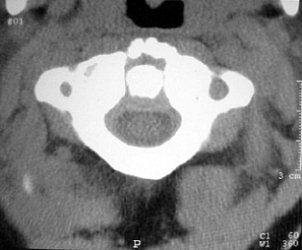

Whichever model is chosen, Cinnamon advised paying attention to the inverse relationship of contrast and spatial resolution, using the following case as an example (images F-G).

![]() |

| Image F |

"On the 2.5-mm slice, you can see the occipital condyle fracture. If (you) go down to the 0.5-mm slice, you can see the fracture just as well -- maybe it looks a little sharper. But you can still identify the fracture on the thicker slice. The value for this is on the coronal and sagittal reformatted images from the 2.5-mm axials. There's a tremendous amount of stair-step artifacts. On the 0.5-mm images, you've eliminated the stair-step artifact because your spatial resolution is so good."